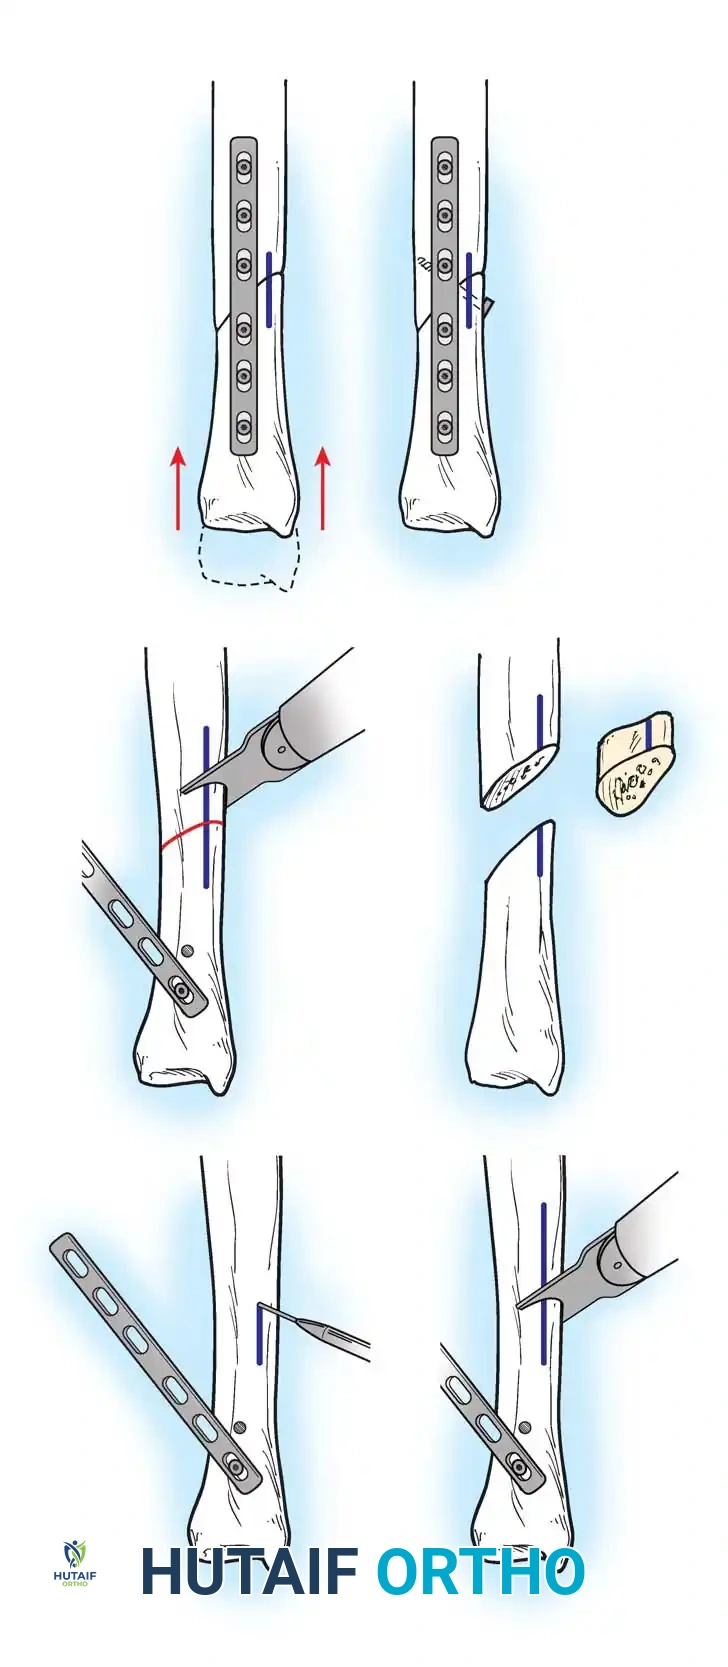

Surgical Technique for Ulnar Shortening Osteotomy:

1. Approach: A longitudinal incision is made over the subcutaneous border of the distal ulna. The interval between the ECU and flexor carpi ulnaris (FCU) is utilized.

2. Plate Application: A specialized ulnar shortening osteotomy plate is applied to the volar or tension surface of the ulna.

3. Osteotomy: A precise oblique or step-cut osteotomy is performed using a cutting guide. The amount of bone resected (typically 2 to 4 mm) is calculated preoperatively based on the degree of positive variance.

Application of a specialized cutting guide to perform a precise, parallel oblique osteotomy of the ulnar diaphysis.

- Compression and Fixation: The osteotomy site is reduced and dynamically compressed using the plate's compression device or an articulated tension device.

The osteotomy is closed and rigidly compressed using a dynamic compression plate, ensuring primary bone healing and immediate structural stability.

- Closure: The periosteum and soft tissues are meticulously closed over the plate to minimize tendon irritation.